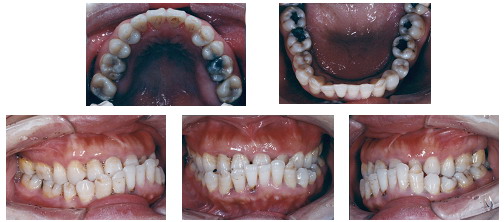

以下是一名38岁女性反合患者的病例,治疗前存在前牙反合、牙弓形态异常、牙弓左右不对称同时伴有颜面骨骼发育异常,面部比例失调,唇突度不协调以及全口不同程度的牙周炎症牙槽骨丧失、上颌尖牙早失,治疗难度很大。经过牙周和正畸的共同努力,在控制牙周炎症之后拔除两颗下切牙,采用目前国际上最流行的MBT矫治技术,经过15个月的治疗,达到了理想的治疗效果。

治疗前